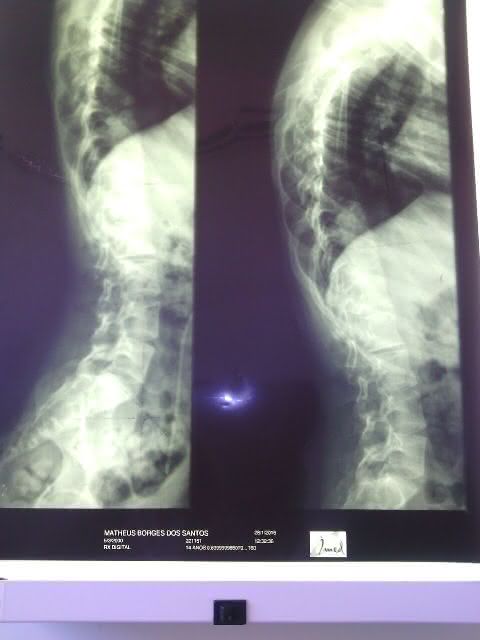

A equipe do portal visitou a residência do vigilante e da professoram que dedicam suas vidas ao pequeno Mateus Domingos dos Santos de 15 anos, que sofre de escoliose que é o encurvamento anormal da coluna vertebral, que provoca dor lombar e nas costas e pode morre caso não consiga realizar uma cirurgia nos próximos meses.

- Raio -X da coluna